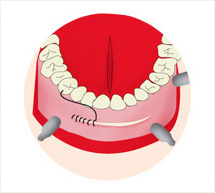

Check 01

Check 01

수면, 부분마취 후 입안절개를 시행합니다.

Check 02

Check 02

골막을 거상하여 보형물이 위치할 공간을 확보합니다.

Check 03

Check 03

확보한 공간에 보형물을 삽입하고 고정시킵니다.

Check 04

Check 04

절개 부위를 봉합합니다.